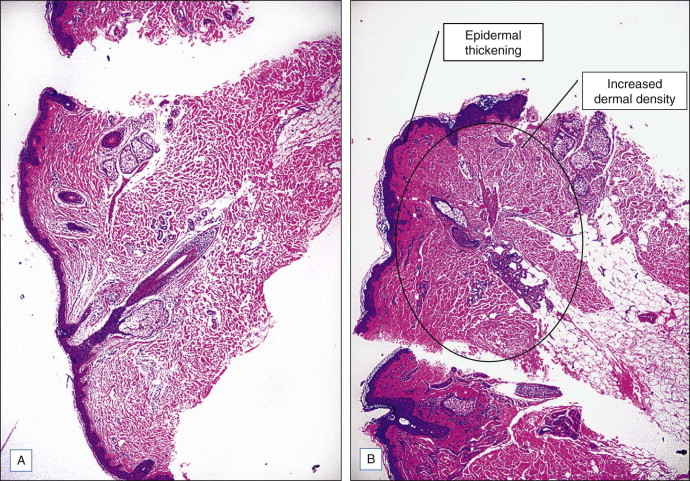

Radiofrequency energy is thought to induce skin tightening of the body by several mechanisms. The first is the immediate contraction of collagen fibers and fibrous septa in the subcutaneous fat due to direct thermal heating. Studies on samples of human abdominal skin have shown that when collagen fibers are heated to specific temperatures with radiofrequency energy, they contract due to breakage of intramolecular hydrogen bonds linking protein chains in the triple helix structure (denaturation). Contraction causes the helix to fold, leading to shorter, thicker, more ‘compact’ collagen fibers. Secondary wound healing also plays a role in tissue tightening with delayed remodeling and neocollagenesis over time ( Fig. 3.1 ). It has been postulated that thermal heating by radiofrequency energy results in a microinflammatory stimulation of fibroblasts which induces new collagen and elastin as well as encouraging collagen reorganization into parallel arrays of compact fibrils. Thus, radiofrequency effects are based on mild heating of the collagen and elastin fibers which can lead to collagen shrinkage and dermal thickening with a resulting improvement in firmness and elasticity of the skin. The degree of tissue tightening is dependent upon several factors, including the maximum temperature reached, the heat exposure time, tissue hydration, and tissue age.